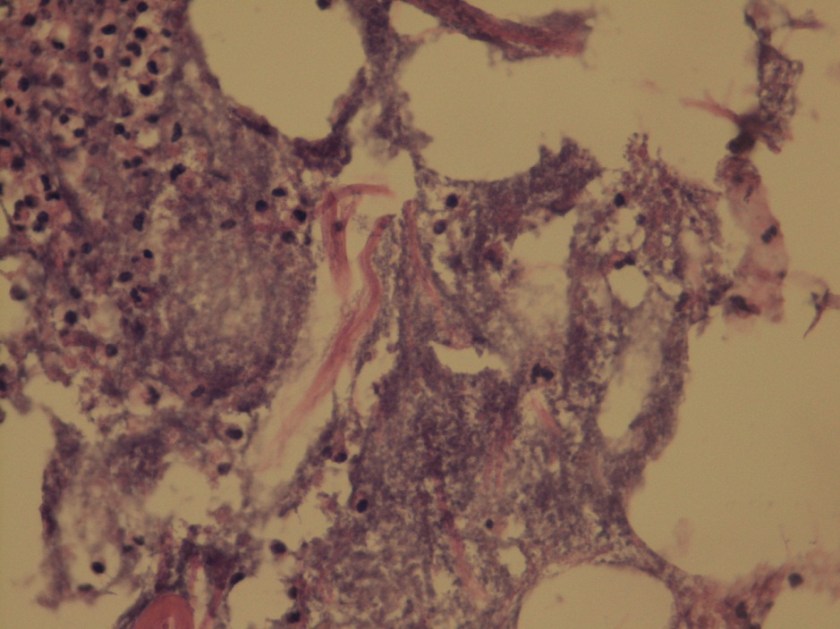

A 72 year old man had been complaining of many months of constipation followed by several months of severe diarrhea prior to admission. He did not receive medical care for these symptoms and had no medical history on file. He presented to an outside hospital unresponsive, and an emergent CT showed subcutaneous emphysema and stranding of the lower abdominal tissue extending to the left hemiscrotum. Also noted was irregular wall thickening in the distal rectum. Of note, his family reported that the patient had hit his left scrotum with a power cord recoil a few days prior to presentation. He was transferred to our hospital, where the surgical team reported severe cellulitis and necrosis of the scrotum, perineum, anterior abdominal wall, and upper thighs. Due to his poor prognosis, the family decided to transition his care to comfort measures only and he passed away several hours after presentation. An autopsy was performed, which revealed liquefaction of the subcutaneous tissue in the lower anterior abdominal wall, dusky gray connective tissue of the left testis as well as a small abscess at the superior pole, and a circumferential distal rectal mass.

A gram stain of the scrotal abscess and tissue of the anterior abdominal wall both showed mixed gram positive and gram negative organisms. Cultures of these specimens both grew mixed gram positives including alpha hemolytic Streptococcus and coagulase negative Staphylococcus, as well as mixed anaerobes including Bacteroides fragilis group.

The case above represents an example of Fournier’s gangrene, a necrotizing infection of the external genitalia and/or perineum. These infections are most often polymicrobial and often include organisms that would not be particularly aggressive by themselves, suggesting a synergy between anaerobic and aerobic organisms. In a large literature review of over 4,000 cases of Fournier’s gangrene, the most common pathogens involved were Escherichia coli, Streptococcus, Bacteroides, Enterobacter, and Staphylococcus. Our case fits well with this profile, consisting of a mixture of gram positives and gram negatives including Streptococcus, Staphylococcus, and Bacteroides fragilis group. Antibiotic coverage in these cases must be broad spectrum and include coverage for aerobes, anaerobes, gram negative and gram positive organisms.

The rectal mass in this case proved to be adenocarcinoma. There have been multiple case reports of Fournier’s gangrene in association with rectal cancer. The theory behind the mechanism of this association is that perforation of the rectal cancer occurs with tumor infiltration of surrounding tissues spreading infectious organisms. It is possible that our case was caused by the patient’s rectal cancer, but it is also possible that the rectal cancer was simply coincidental. The recent trauma to the patient’s scrotum could also have acted as a vector for infection.